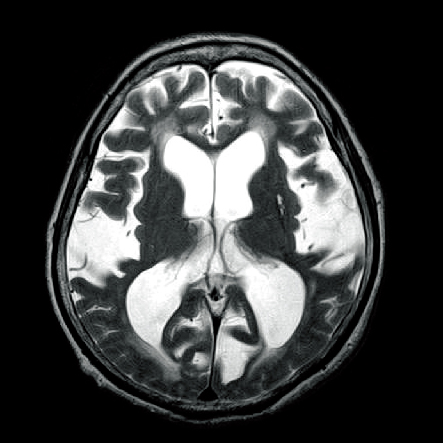

2)MRIでの水頭症の鑑別

MRIで撮影すると、T1強調像では図1-3のように描写され、CTと比較してより鮮明に脳室やくも膜下腔が拡大していることがわかります。T2強調像では図1-4のように描写され、脳室周辺の脳浮腫を認めています。

●T1強調像では、髄液は黒く映る( 低信号域)

●T2強調像では、髄液は白く映る(高信号域)

●脳室周辺に淡い高信号域が描写され、脳室拡大による脳浮腫が生じている

図3において側脳室が通常より拡大しており、正常圧水頭症を起こしています。

くも膜下出血慢性期に生じる水頭症は脳室の拡大を認めますが、急性水頭症のときに描写されていた血液は頭蓋内からなくなり、画像上では描写されません。

本症例は前交通動脈の動脈瘤破裂によるくも膜下出血(Hunt&Hess分類GradeⅤ)の、発症1年後の状態です。

くも膜下出血の慢性期で生じる正常圧水頭症は、急性水頭症の「交通性水頭症」の病態が緩徐に進行し、慢性的な髄液の循環障害が起こることで引き起こされます。

くも膜下出血慢性期の正常圧水頭症は交通性水頭症に分類され、通常、頭蓋内圧が亢進しないのが特徴です。そのため、くも膜下出血急性期の合併症の急性水頭症とは違い頭蓋内圧亢進症状はみられません。